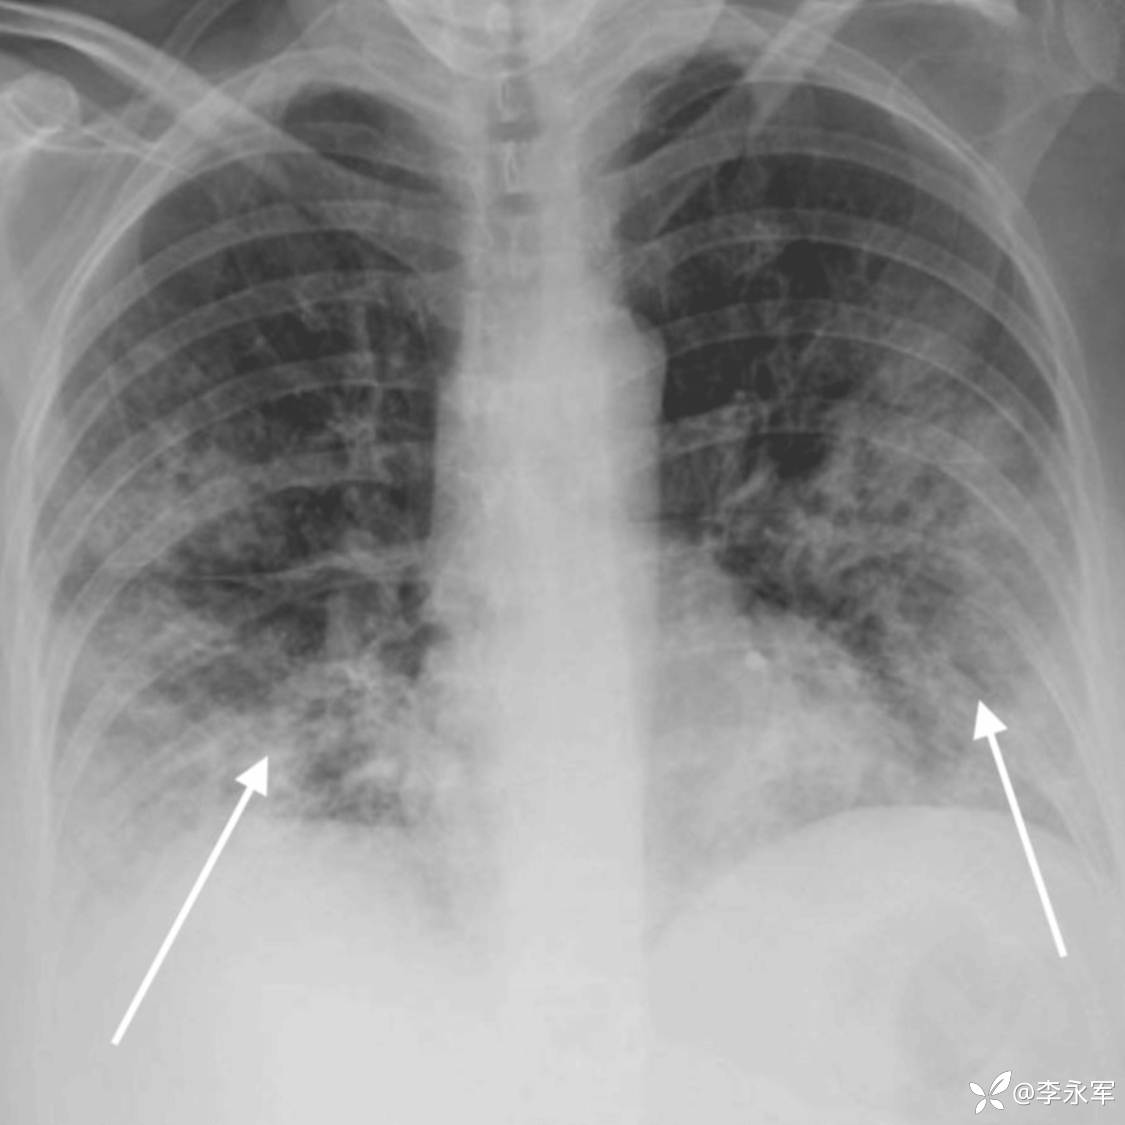

高流量鼻导管氧疗下的复查动脉血气显示呼吸性碱中毒缓解,氧合改善(PaO2 = 73 mmHg,SpO2 = 95%)。听诊显示双侧呼吸音清晰,伴弥漫性干啰音。复查胸部 X 光片和 CT 扫描显示双侧斑片状浸润影,符合 ARDS 表现,并怀疑叠加细菌感染。实验室结果显示 CRP 显著升高至 283.9 mg/L,白细胞计数下降至 3.33 x 10^9/L。考虑到她的 PaO2/FiO2 比值为 73(在使用 100% FIO2 和 60 升/分钟流速下),符合更新版全球定义中 ARDS 的诊断标准。

图 2:入院时胸部 X 光片